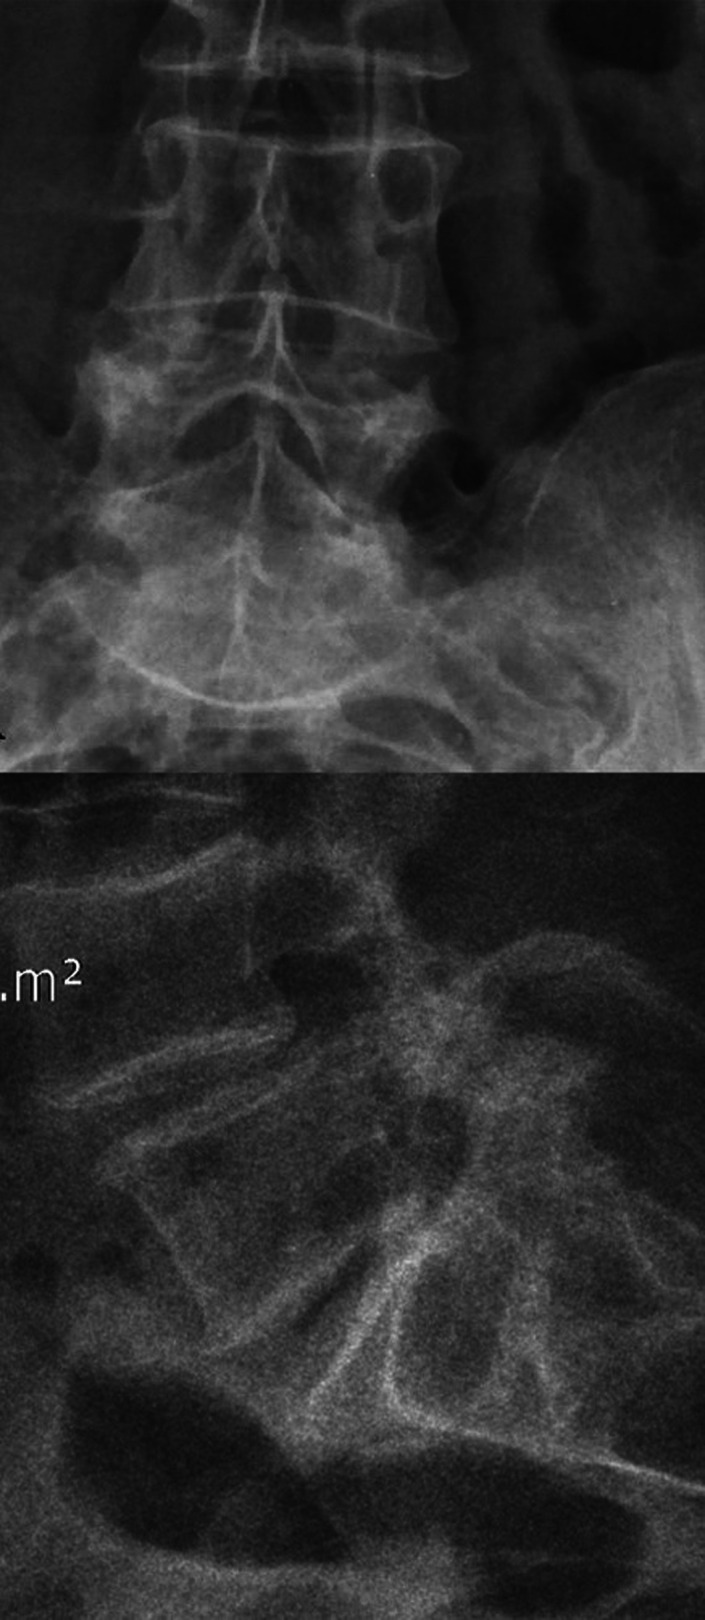

Methods: Sixteen patients with mono-segmental disc degeneration (L4-L5 or L5-S1) who underwent posterior lumbar spine fixation with intervertebral distraction of 2 consecutive vertebrae using monoaxial transpedicular screws and lyophilized allograft to achieve segmental fusion, and who had a follow-up period of at least 2 years, were included in this study. The first lumbar disc was used as the control group. The dGEMRIC studies in degenerative and control discs, visual analogue scale (VAS), Oswestry disability index (ODI), lumbar lordosis, and disc thickness were reviewed before and after surgery.